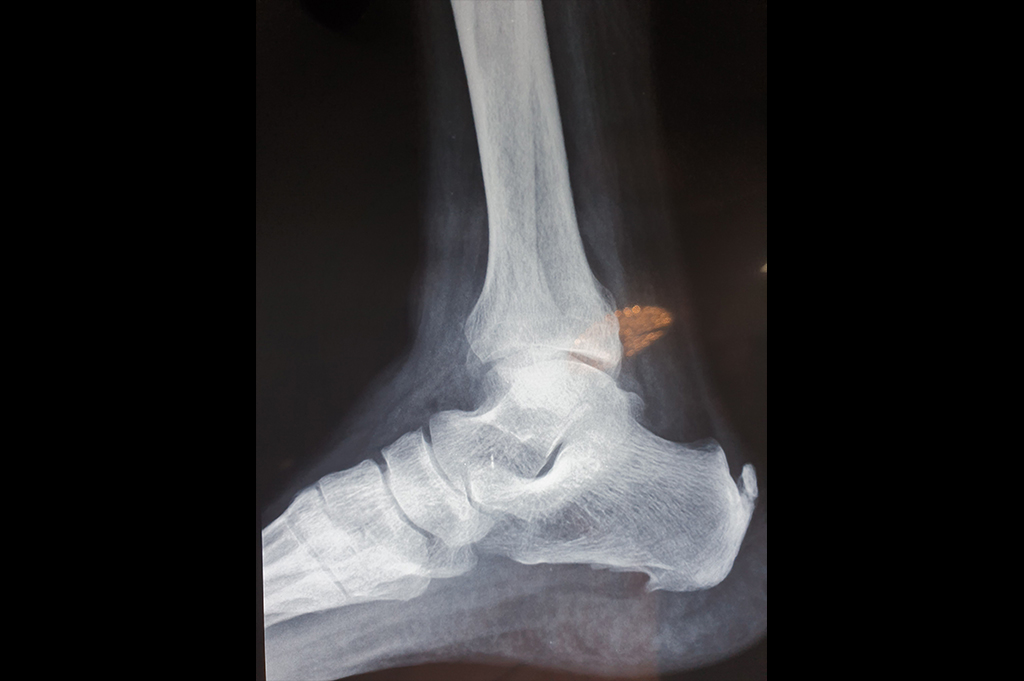

Ankle